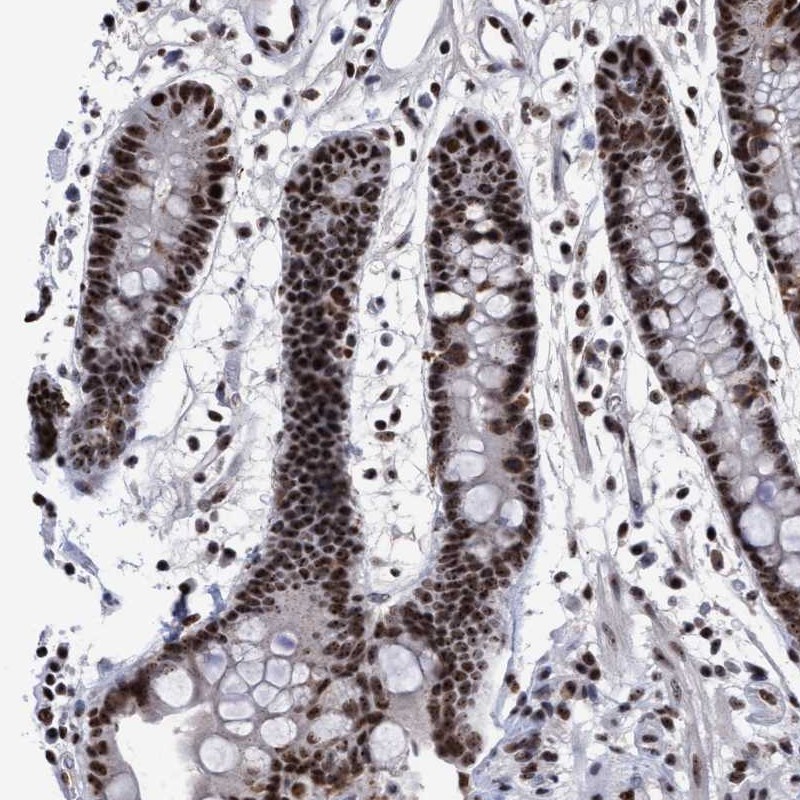

Immunohistochemical staining of human colon shows strong nuclear positivity in glandular cells.